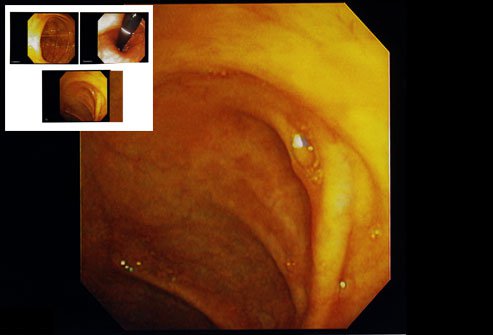

A chromoendoscopy is a diagnostic procedure in which a chemical substance (called a stain or pigment) is sprayed inside the gut to highlight specific areas or distinguish among the different types of cell layers. This helps visualize the inner surface of the bowel (epithelia) during endoscopy. Chromoendoscopy is a simple, cost-effective, quick, and safe diagnostic method that improves the recognition of the tiny changes in the surface pattern. It does this by enhancing the contrast of raised and deepened areas.

Three types of stains can be used for chromoendoscopy:

- Absorptive or vital stains: These stains diffuse or are selectively absorbed across specific epithelia (e.g., Lugol's solution and methylene blue).

- Contrast stains: These stains highlight surface irregularities (topography) of the inside of the gut by filling the mucosal crevices (e.g., methylene blue).

- Reactive stains: As the name suggests, these stains undergo chemical reactions with specific cell components, resulting in a color change (e.g., congo red and phenol red).